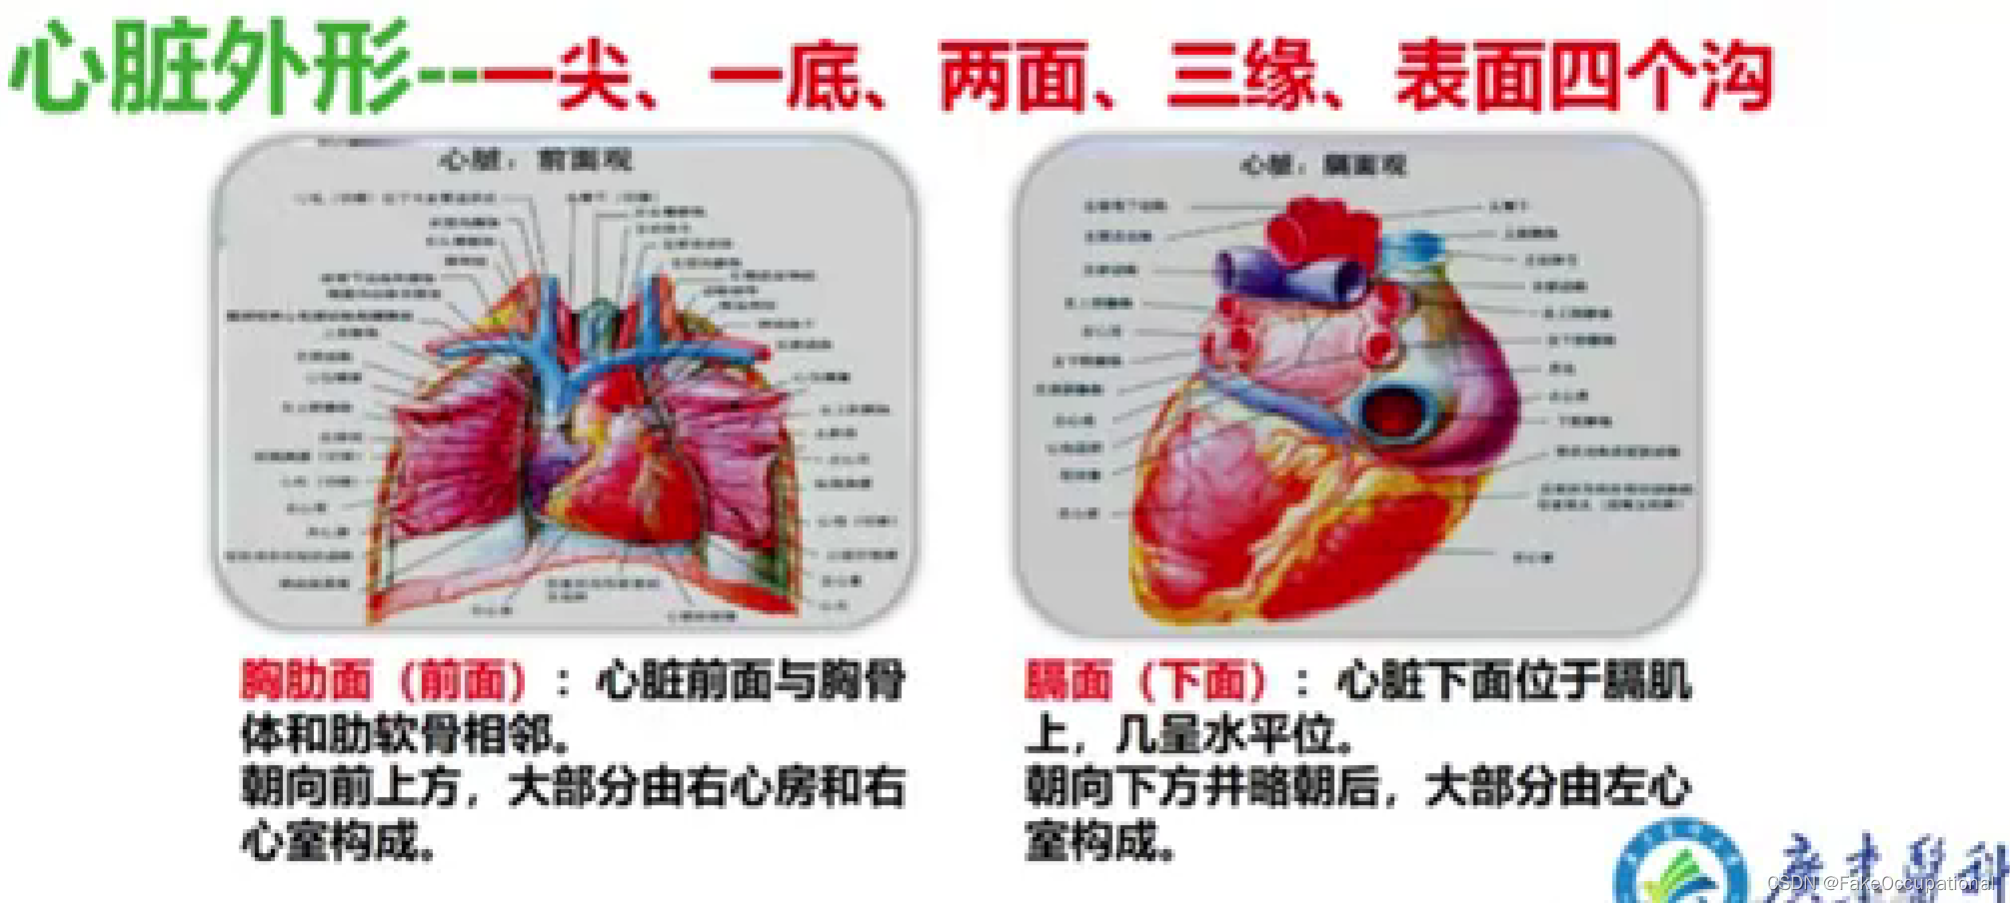

心脏解剖及生理概要